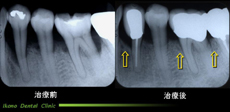

上顎奥歯インプラント

当院での治療例(クリックで拡大)

上あごにインプラントを埋入するのに十分な骨がありませんでした。まずインプラントが埋入できる骨を造成してインプラントを植立しました。

インプラントを埋入だけでなく、歯周病の治療、噛み合わせの治療、といった病院の総合力が要求されます。